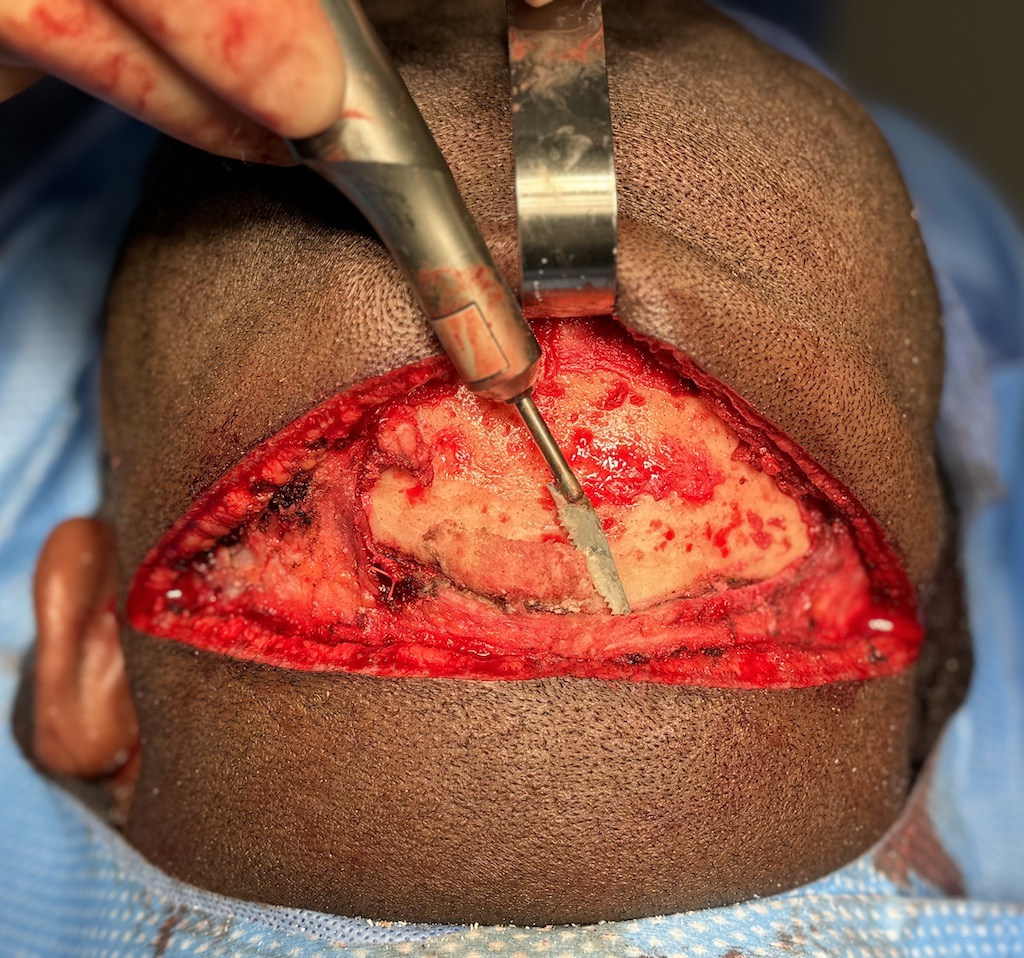

Desire for reduction of prominent occipital knob deformity.

Intraoperative result from occipital knob skull reduction through a direct small scalp incision.

Desire for reduction of prominent occipital knob deformity.

Intraoperative result from occipital knob skull reduction through a direct small scalp incision.